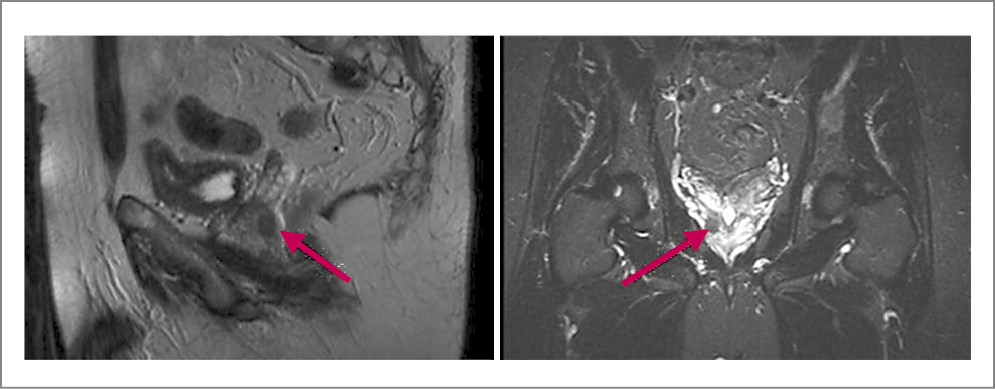

По данным МРТ органов малого таза с контрастированием установлено, что предстательная железа не увеличена – 3,1×4,4×4,0 см. В периферической и транзиторной зонах правой доли на уровне верхушки и среднего сектора имеется зона пониженного сигнала – 2,2×1,0×1,7 см – с ранним накоплением контраста. Распространения за пределы капсулы нет. Парааортальные и забрюшинные лимфоузлы не увеличены. Магнитно-резонансная картина соответствует 5-й категории изменений по шкале PI-RADS (PI-RADS 5) – очень высокий риск (наличие клинически значимого рака крайне вероятно); рис. 3.

Рис. 3. Больной Л., 66 лет. МРТ органов малого таза. Образование в правых отделах периферической зоны предстательной железы без признаков распространения за пределы органа размером 2,2×1,0×2,7 см (стрелки). PI-RADS 5.

В левой подвздошной кости выявлено объемное образование размером 2,4×1,3 см метастатического характера, накапливающее контраст (рис. 4).

Рис. 4. Больной Л., 66 лет. МРТ органов малого таза. Контрастпозитивное образование вторичного характера в левой подвздошной кости (стрелки).